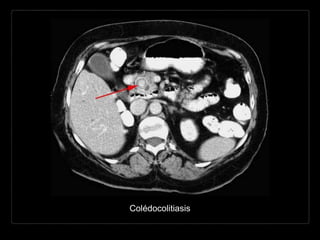

COLÉDOCOLITIASIS

Hallazgos por TC

• densidad del cálculo

aire - < agua - tejidos blandos -

calcio

• mixtas: anillo calcificado y nido central

• ↑ atenuación (75-85%)

• signo “ojo de buey”: anillo de bilis rodeando un cálculo en un

conducto

• colesterol puro = isodensas con la bilis

• terminación abrupta del colédoco

• dilatación de la VBIH y EH

• Cálculos

• posición posterior (dependiente)

• semiluna de bilis o aire rodeando la

porción anterior del cálculo

• forma geométrica o angulada

• apariencia multilaminar

• signos de inflamación

• edema periductal, engrosamiento

epitelial biliar y reforzamiento

mural.

• mejor valoración

• cortes delgados y MPR

• contraste oral (-) > (+)

• oscurecimiento litos

ampulares

• parámetros altos del

tubo 140 kVp

• litos hiperdensos >

bilis